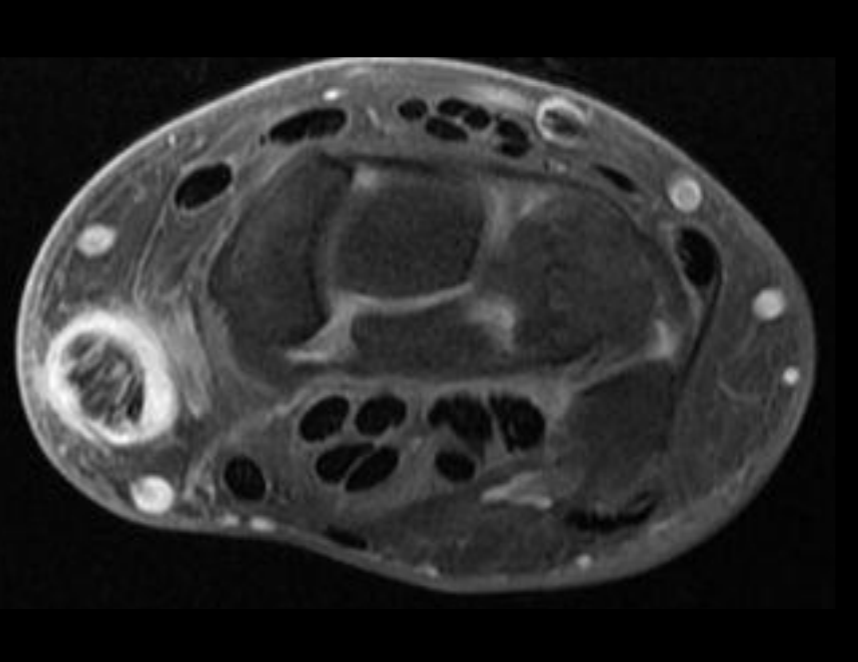

RM Sx Tunel del Carpo

Nervio aplanádo hiperintenso

Captación de contraste